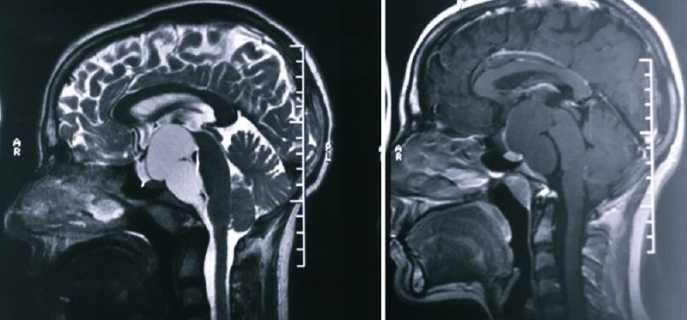

Диагностика

Постановка правильного диагноза – одна из важнейших составляющих лечения. При неправильном подходе есть риск летального исхода. Так, в случае, когда злокачественную опухоль путают с такой кистой, могут назначить проведение хирургической операции, чего делать ни в коем случае при опасных опухолях нельзя.

Сначала врач проводит опрос, составляя полную картину симптомов пациента. После этого обязательно назначаются КТ, МРТ и УЗИ, при этом последнюю процедуру проходить нужно с внутривенным введением контрастного вещества, что поможет определить злокачественная или доброкачественная опухоль у больного. Также врач назначает другие обследования, чтобы точно определить причину образования кисты. Важно сделать это сразу, чтобы быстро начать лечение и исключить повторное негативное воздействие первопричины.

Сразу после выявления расширения ретроцеребеллярного пространства и постановки диагноза больному назначается лечение. Необходимо приступить к нему максимально быстро, чтобы исключить дальнейшее ухудшение состояния и всевозможные риски.